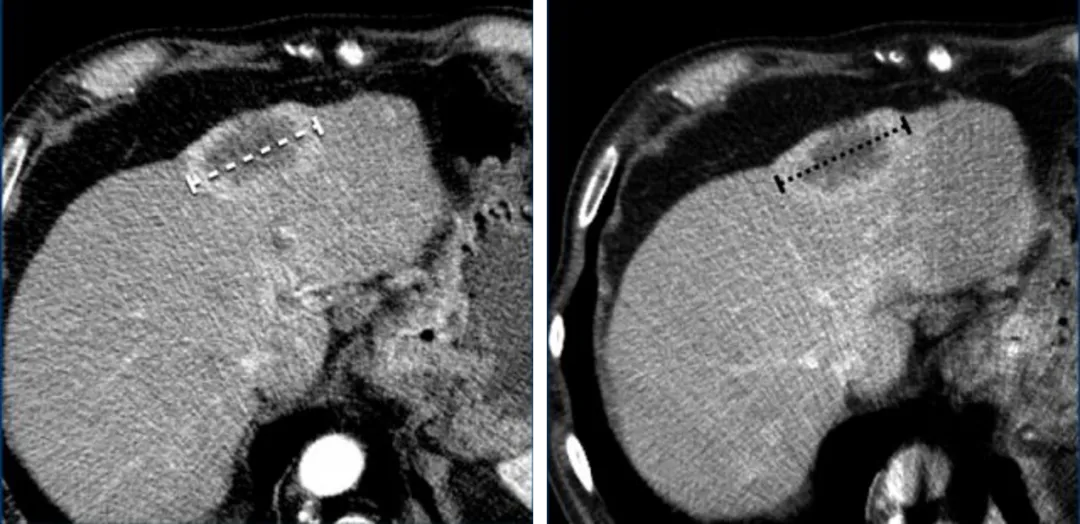

一名71岁男性,腹部增强CT检查显示食管神经内分泌肿瘤的肝转移,

动脉期(左)更清楚地显示出环形强化边缘,测量时应将其包含在最长径的测量值中。